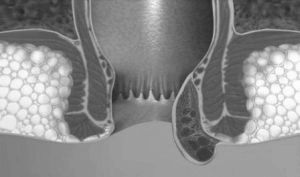

Це неинфекционное захворювання, але воно характеризується запальним процесом, в результаті якого спостерігається збільшення вен патологічного характеру. Перша ознака - поява шишок або гемороїдальних вузлів.

Шишки можуть утворюватися різних розмірів і знаходяться вони навколо товстої кишки.